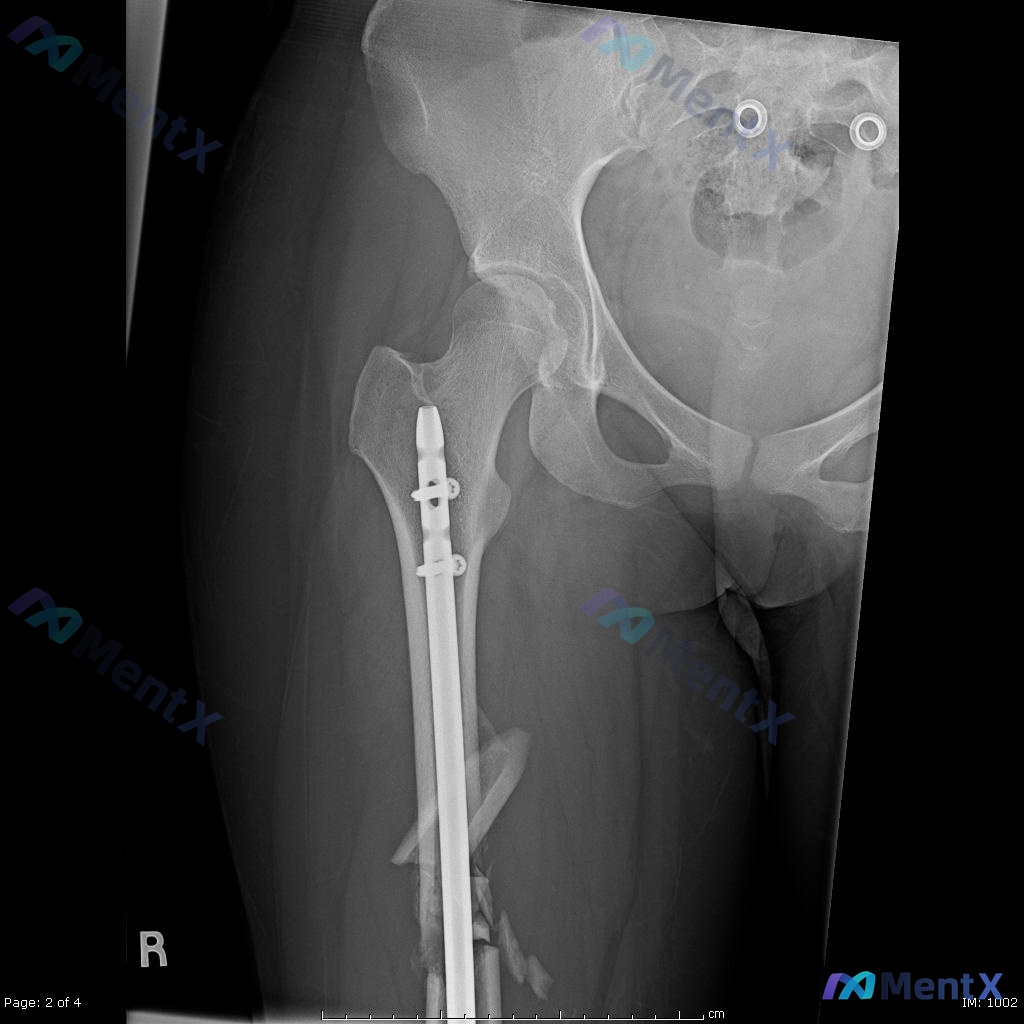

看到一个挺有代表性的创伤骨科病例,结合影像和临床分析整理了一下思路,关于「髓内钉固定术后负重时机」的误区其实还挺普遍的。 --- 一、先把病例核心信息捋清楚 基本情况:22岁男性,高能量车祸受伤 影像关键所见: - 术前(图A/B):右侧股骨干中段粉碎性骨折,多块游离骨块,移位明显;局部软组织肿胀;...